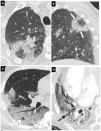

Vasos prominentes: dilatación de los vasos pulmonares peri- o intralesionales (fig. 8A) por daño de la pared capilar en respuesta a factores inflamatorios50.

Figura 8.Hallazgos típicos de neumonía COVID-19 en tomografía computarizada (TC). Imágenes axiales de TC de tórax con cortes de 1mm. A) Engrosamiento vascular (flecha) asociado a un área de opacidad en vidrio deslustrado (asterisco). B) Línea curvilínea subpleural (flecha). C) Bandas parenquimatosas subpleurales (flechas). D) Línea hipoatenuante (flechas) entre la pleural visceral y la opacidad en vidrio deslustrado (puntas de flecha).

- •

Alteraciones pleurales y subpleurales:

- –

Engrosamiento pleural asociado a las alteraciones del parénquima pulmonar.

Línea curvilínea subpleural (fig. 8B): opacidad curvilínea fina con un grosor de 1 a 3mm, localizada paralela a la pleura y a menos de 1cm de la superficie pleural. Se relaciona con edema o fibrosis53.

Banda parenquimatosa subpleural (fig. 8C): opacidad lineal, habitualmente de 1-3mm de grosor y de hasta 5cm de longitud, localizada perpendicular a la pleura visceral, hasta la que se suele extender, que a menudo está engrosada y retraída en el punto de contacto. Refleja una fibrosis parenquimatosa y se asocia habitualmente a distorsión de la arquitectura pulmonar.

Línea hipoatenuante entre la pleura visceral y la lesión (fig. 8D).

Evolución de neumonía COVID-19 en mujer de 56 años. Imágenes axiales de tomografía computarizada (TC) de tórax de 1mm de espesor a la altura de la carina. A) Estudio a los 10 días del comienzo de los síntomas. Opacidades en vidrio deslustrado periféricas y bilaterales (puntas de flecha) y pequeña consolidación en formación en el segmento posterior del lóbulo superior derecho (flecha). B) TC a los 15 días después de realizarse la primera. Evolución de las opacidades en vidrio deslustrado a consolidaciones (flechas). C) TC a los 32 días después realizarse de la primera. Reabsorción parcial de las consolidaciones (puntas de flecha) y engrosamiento pleural focal en el segmento ápico-posterior del lóbulo superior izquierdo (flecha negra).